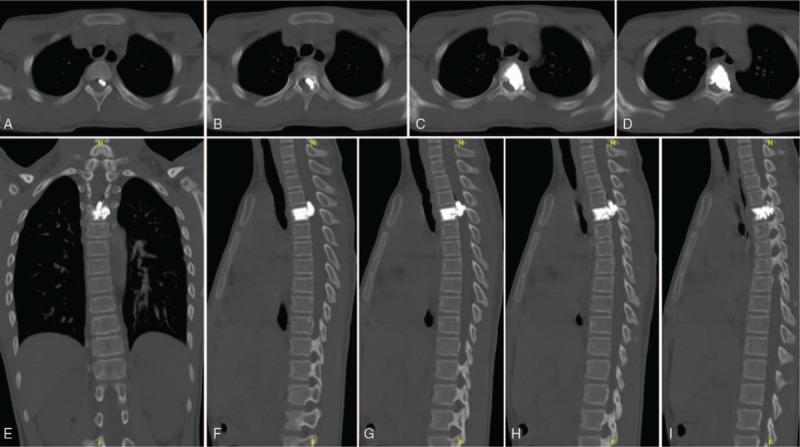

Magnetic resonance imaging of spine and positron emission tomography-computed tomography showed spinal cord compression secondary to the epidural component of the T4 mass, with increased marrow infiltration of the left T4 intervertebral foramen, which was difficult to be removed. Postoperative pathology confirmed the diagnosis of spinal involvement of malignant paraganglioma.

The patient underwent biopsy and percutaneous vertebroplasty of T4 and paravertebral lesions, and needle-track cement augmentation via a posterior approach.

脊柱磁共振成像和正电子发射断层扫描 - 计算机断层扫描显示T4肿块硬膜外成分导致脊髓受压,左侧T4椎间孔骨髓浸润增加,难以切除。术后病理证实为恶性副神经节瘤脊髓受累。

患者接受了T4及椎旁病变的活检和经皮椎体成形术,并通过后路进行针道骨水泥强化。